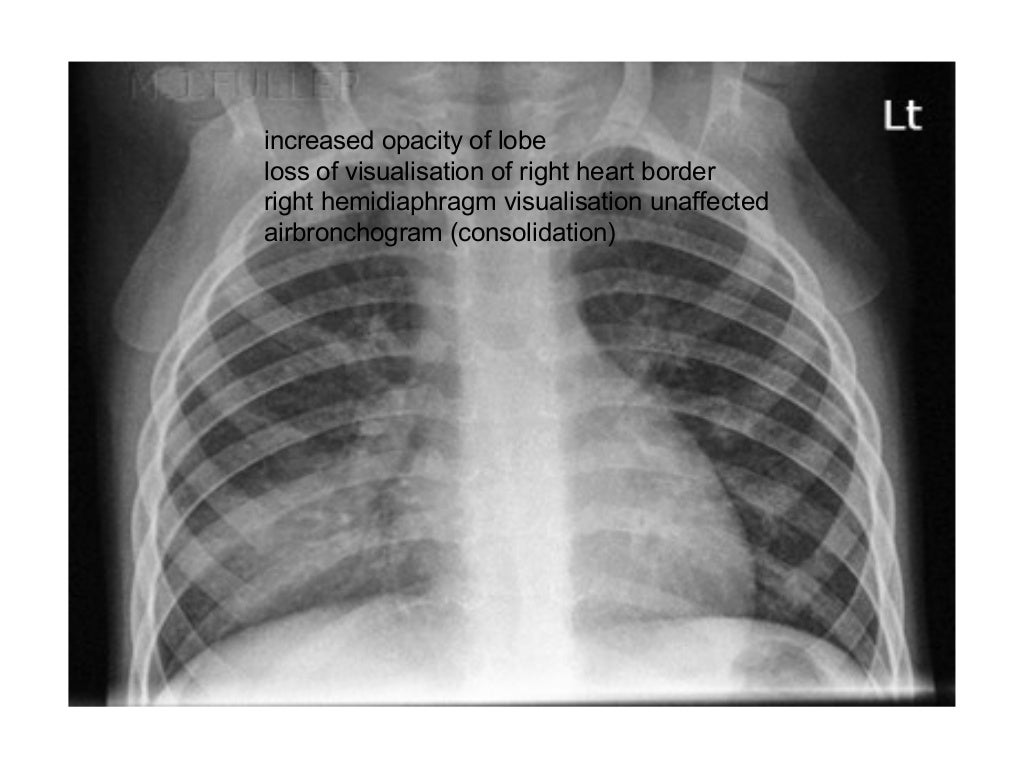

Chest Xray showing rightsided consolidation. Download Scientific Types Of Consolidation Chest X Ray consolidation is a type of airspace disease that obscures the lung vasculature on chest radiography. consolidation is increased lung attenuation that obscures bronchial walls and blood vessels on ct. Learn how to identify consolidation on. consolidation is the replacement of gas within the airspaces by fluid, protein, cells, or other material. Learn about the causes, patterns, signs,. Types Of Consolidation Chest X Ray.